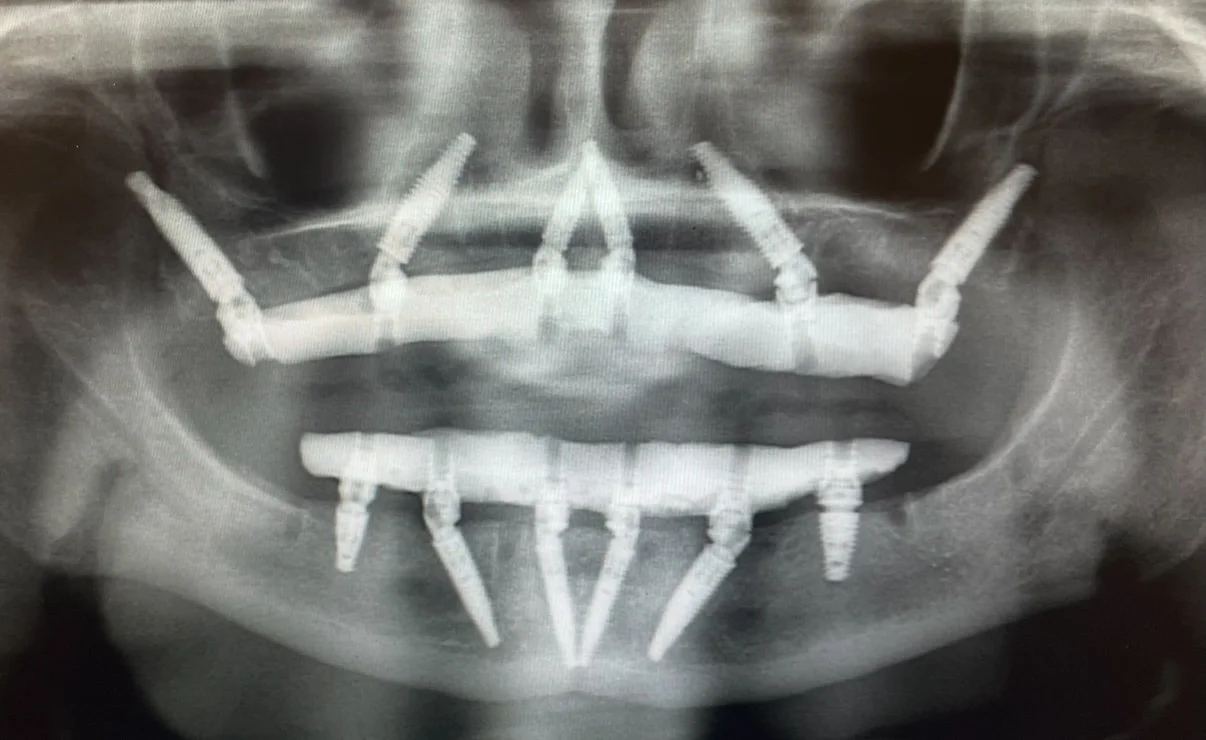

Dr. Damons Cases